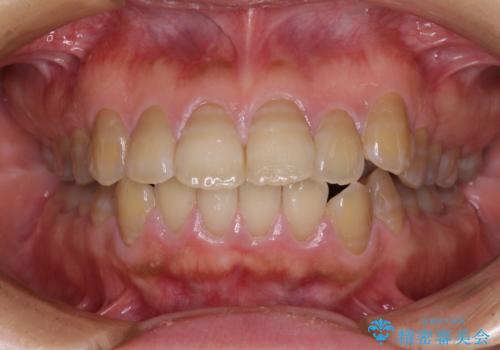

【モニター】処置歯の多い歯列 インビザラインでデコボコを整える